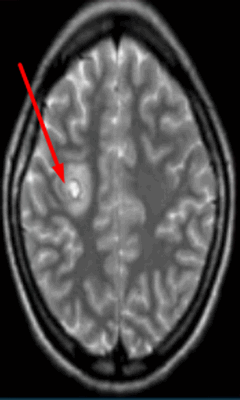

Туберозный склероз. Гамартомы. КТ, Т2-зависимая МРТ и FLAIR

Корковые узлы - самое частое проявление туберозного склероза. Они расположены в коре головного мозга, деформируют её, захватывают прилегающее белое вещество и подвергаются кальцификации . При МРТ узлы изоинтенсивны серому веществу на Т1-взвешенных МРТ и чуть гиперинтенсивнее его на Т2-взвешенных. Контрастирование наблюдается в 5% случаев. В белом веществе обнаруживаются тяжи , отходящие радиально от желудочков. Корковые узлы и тяжи нередко называют «гамартомами», хотя они представляют собой скорее демиелинизацию и кальцификацию, чем истинную гетеротопию.

Туберозный склероз (синдром Бурневиля) встречается реже нейрофиброматоза. Его частота по данным литературы составляет около одного на 180 тыс. населения. От 20 до 40% случаев туберозного склероза унаследованы по аутосомно- доминантному типу, остальные возникли вследствии мутаций предположительно 9 и 11 пар хромосом (тип 1), либо 19 пары (тип 2). Поражение может затрагивать практически любые органы. Патогномоничными поражениями ЦНС являются корковые узлы в головном мозге и множественные субэпендимальные глиальные узлы , а также внутрижелудочковая гигантоклеточная астроцитома, встречаются сопутствующие аномалии - агенезия мозолистого тела, пахигирия, аневризмы. Характерны дерматологические проявления в виде множественных ангиофибром лица в форме «бабочки», бледные пятна на лице и груди, фибромы кожи, под ногтями и сетчатке глаза. Из других проявлений встречаются множественные ангиолипомы почек и печени, рабдомиомы сердца, лимфангиоматоз лёгких, костные склеротические и кистозные изменения. Диагноз туберозного склероза ставится при наличии у пациента 2 из перечисленных характерных признаков.